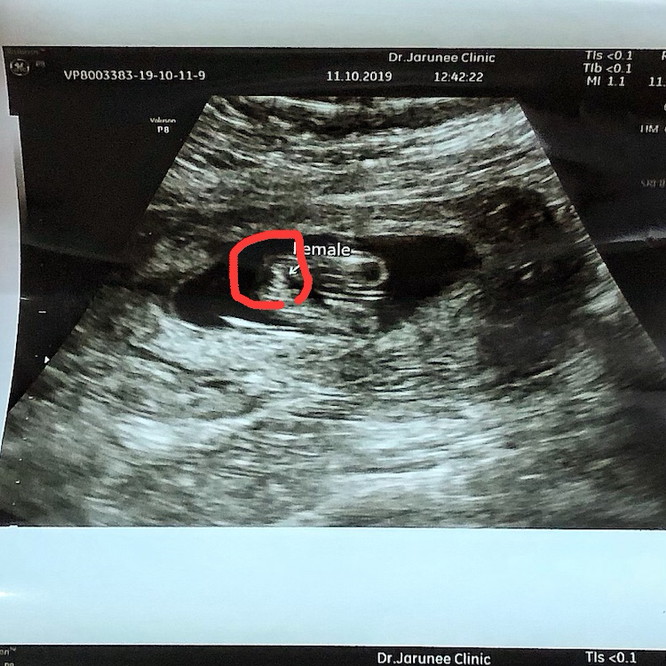

อัลตร้าซาวดูเพศ

หมอให้ใบอันตร้าซาวมาใหมค่ะ พึ่งซาวมา เห็นเป็นกลีบน่ะค่ะ แต่มี2อัน เห็นแบบที่หนูเห็นไหมค่ะ

บ้านนี้จ้า อัลตร้าซาวน์3รอบบอกได้ผู้หญิง คลอดมาน้องเป็นผู้ชายค่ะ ฮามาก😂